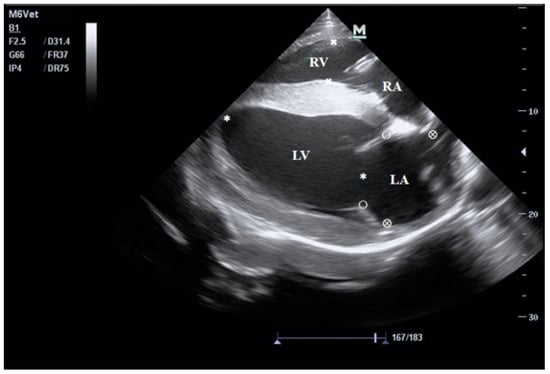

2.3. Echocardiography and Blood Sample Collection

3.1. Echocardiographic Parameters of Horses